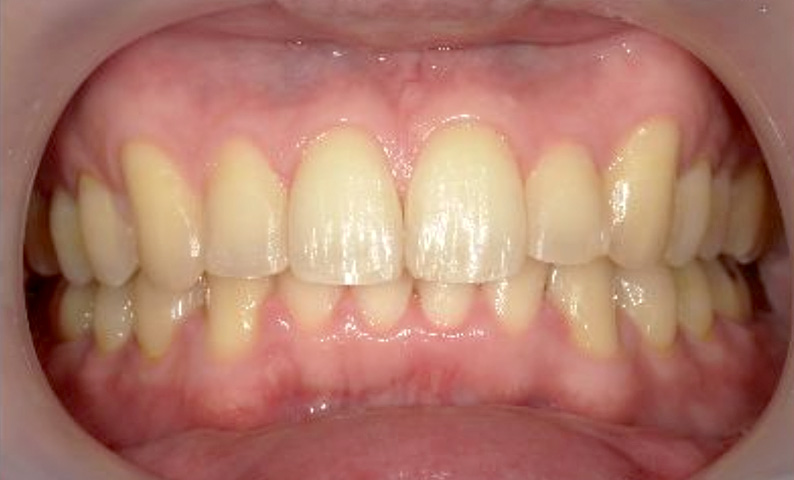

症例_030 上下顎の部分矯正

治療期間:12ヶ月金額:54万円+税女性八の字/V字型捻転歯前歯のガタガタ